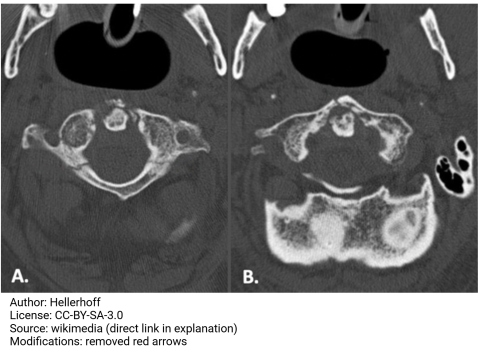

Dr. Ake, a 37-year-old professional rapper, is enjoying his beautiful lagoon-style pool at his Toronto mansion. He makes his pool staff take a short video of him diving straight down into the pool from the shallow end to impress his fans. Gotta do it for the 'gram! Unfortunately, Dr. Ake emerges from the pool with neck pain and dizziness after hitting his head on the bottom. Just in case, Dr. Ake has his personal on-call physician do a full workup. An axial CT series of his cervical region is shown in the accompanying image. What is the most likely diagnosis?

Poor Dr. Ake, am I right? If you picked a Jefferson burst fracture, you nailed it. This type of injury is also known as a traumatic spondylolysis of C1. The CT images show fractures of the anterior and posterior arches of C1 (remember, C1 does not have a vertebral body!). The little nubbin articulating with the anterior arch is the dens of C2. The most likely etiology of a Jefferson burst fracture is trauma from above, like diving into a shallow pool, in which impact to the top of the skull (i.e., from hitting the pool bottom) translates through the occipital condyles and splits the atlas apart. Eesh.

Hangman's fracture, Nope. A Hangman's fracture is also known as traumatic spondylolysis of C2. The etiology is typically a hyperextension injury, such as hitting your chin on the steering wheel of your car during a car accident. Dr. Ake suffered a C1 injury, as indicated by the mechanism of injury and the CT scans shown. Good try, though!

Fracture of the dens: You don't even have the right view of the dens to tell if it's fractured. Try a lateral x-ray or sagittal CT. In this case, there is not enough evidence to suggest that Dr. Ake's dens was fractured. His C1 is clearly in shambles, though.

Anterior dislocation of C1: Nah. Anterior dislocation is most likely due to rupture of the transverse ligament of the atlas, holding the anterior arch of the atlas up against the dens. The CT images show the dens nice and snug up against the anterior arch of C1!

Bow Hunter Syndrome is highly unlikely; Bow Hunter Syndrome refers to compression of the vertebral artery due to prolonged or forceful head rotation. Symptoms include dizziness and fainting. Dr. Ake didn't keep his head turned for too long - he made a dumb move and dove headfirst into a shallow pool. While his fractured C1 may result in vertebral artery compression from bone fragments, the vertebral foramina looks pretty clear in the accompanying CT images. Bow Hunter Syndrome really isn't likely here.

Cervical spinal stenosis: I can see where you're going with this - often, vertebral injuries result in motor or sensory deficits due to spinal stenosis. In this case, however, spondylolysis of C1 from a superior impact typically bursts the bone fragments apart, actually making stenosis LESS likely. His spinal cord is most likely fine, assuming his doc gets him stabilized in time.